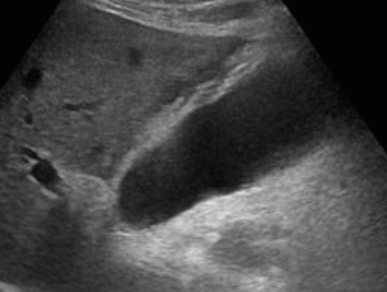

US finding

- 담낭주위 띠모양의 경계가 좋은 액체저류가 보인다

- 담낭은 경계가 불분명해지며 팽팽해진다

- 심한 경우 저에코성 종괴들이 관찰된다